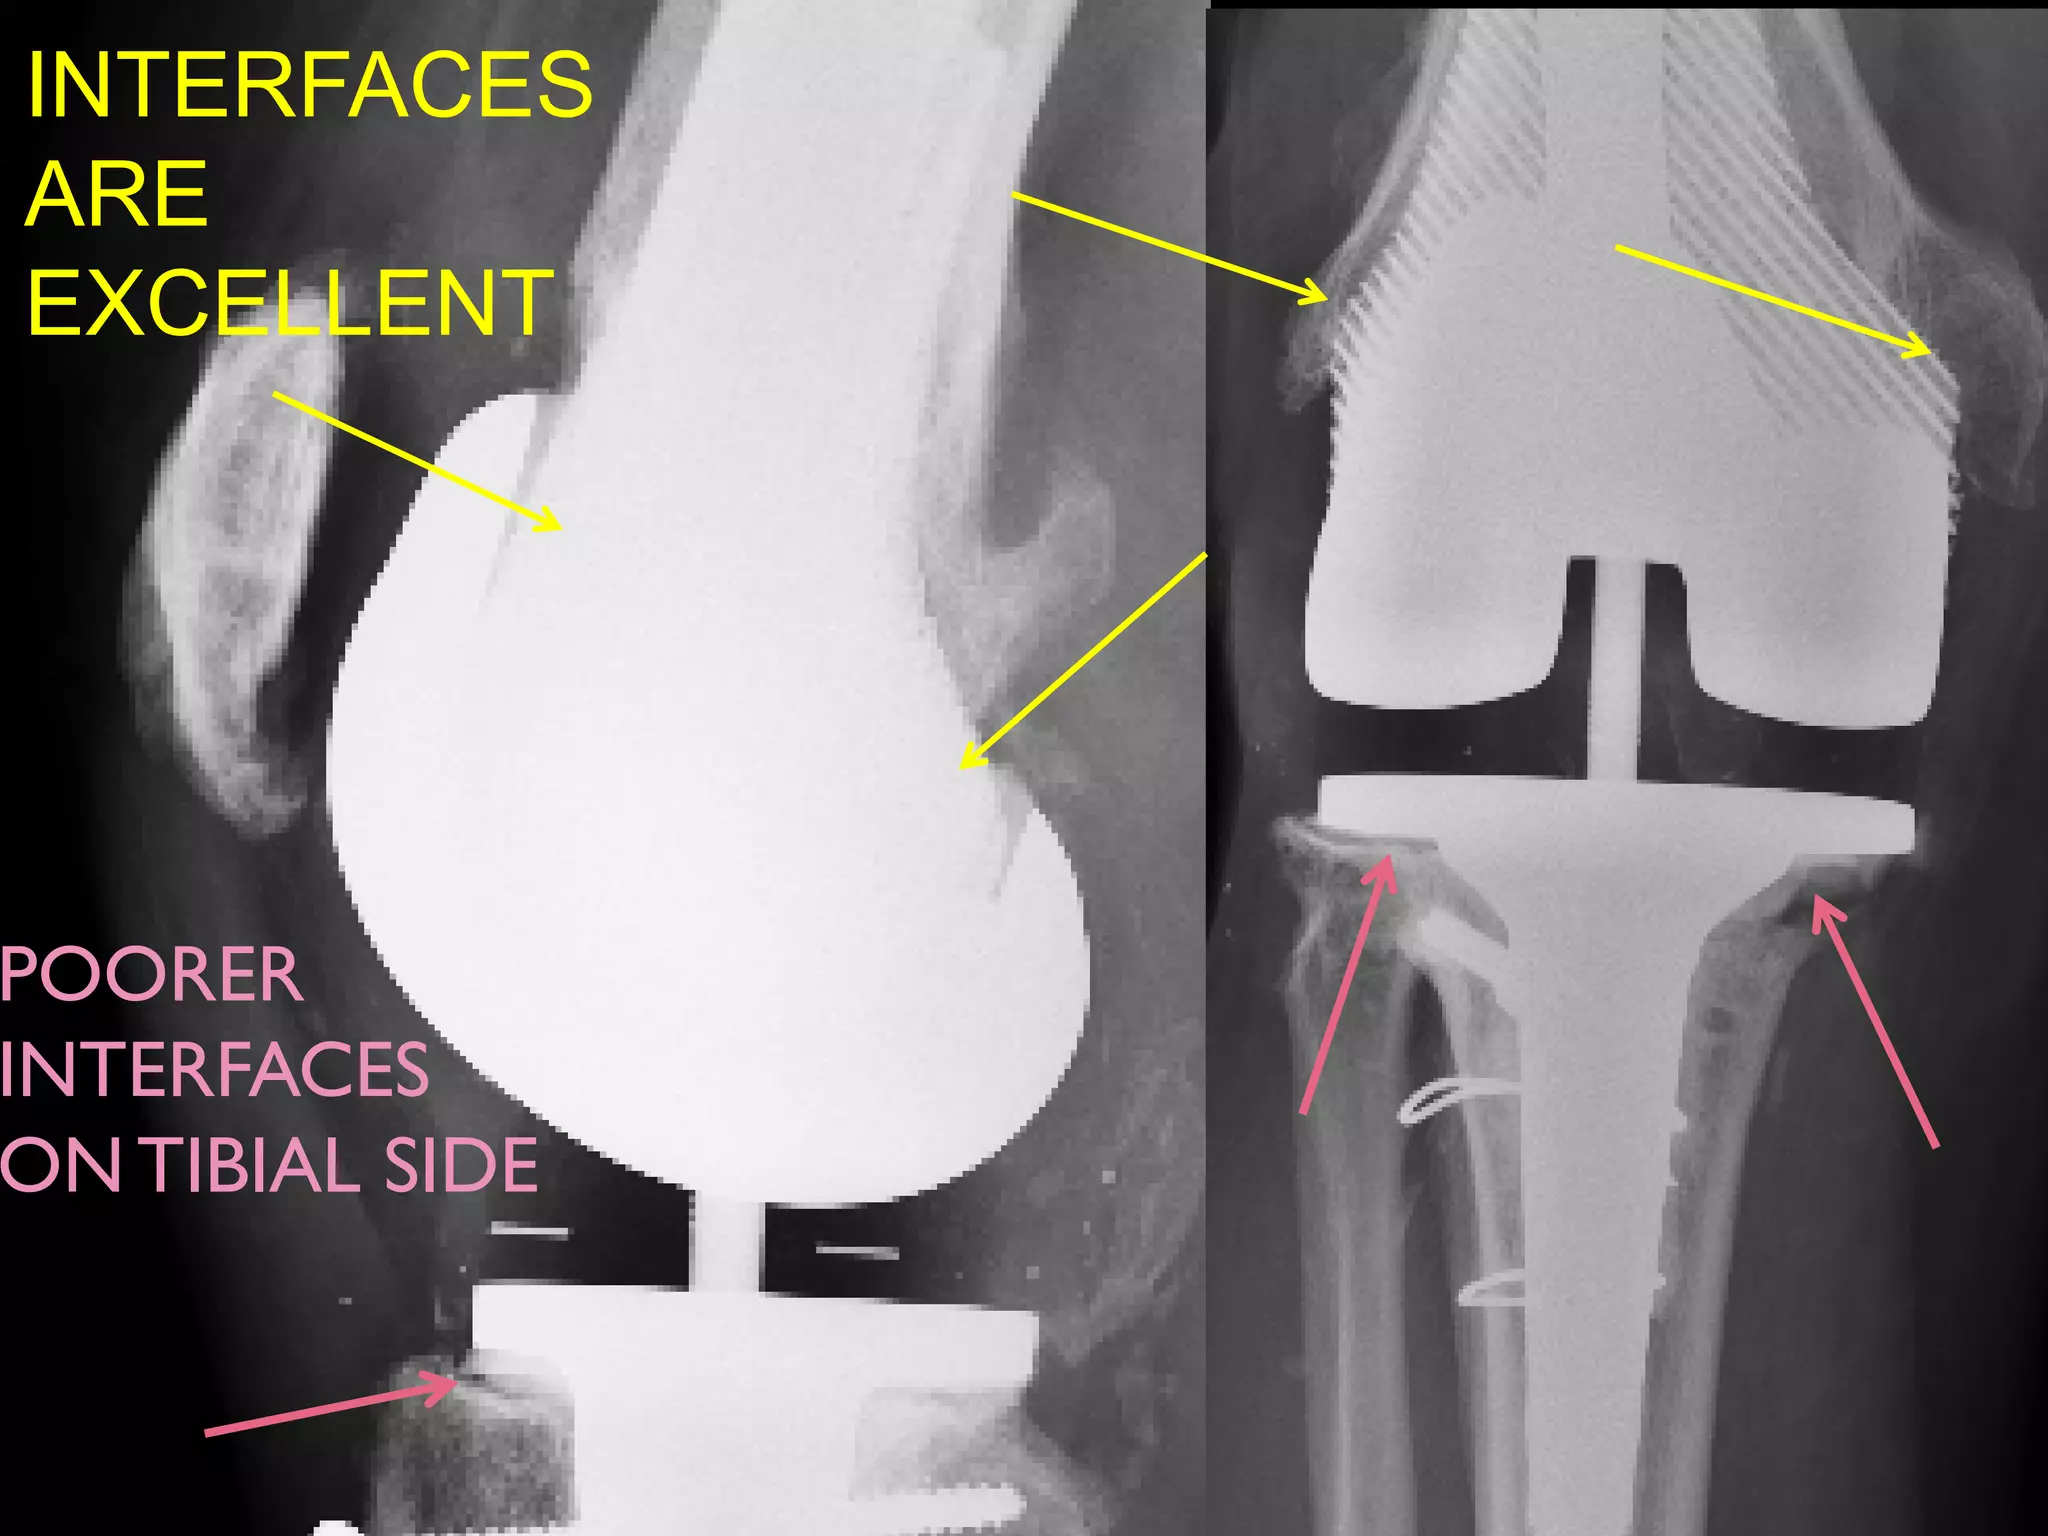

THE EBMTi ALLOY AUGMENT:

PRIMARY KNEE AND STEM (2008)

A HUGE CAVITY BUT A GOOD SOLUTION

INTERFACES

ARE

EXCELLENT

POORER

ON TIBIAL SIDE

THE EBMTi ALLOYAUGMENT: PRIMARY KNEE AND STEM (2008)

A HUGE CAVITYBUT A GOOD SOLUTION